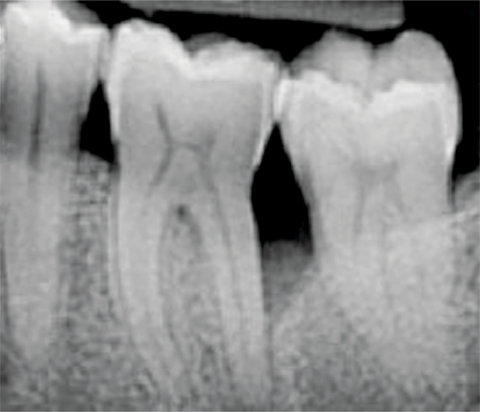

Chirurgische Behandlung eines intraossären Defekts mit xHyA unter Beobachtung einer schnellen Wundheilung

Prof. Pilloni

Italien